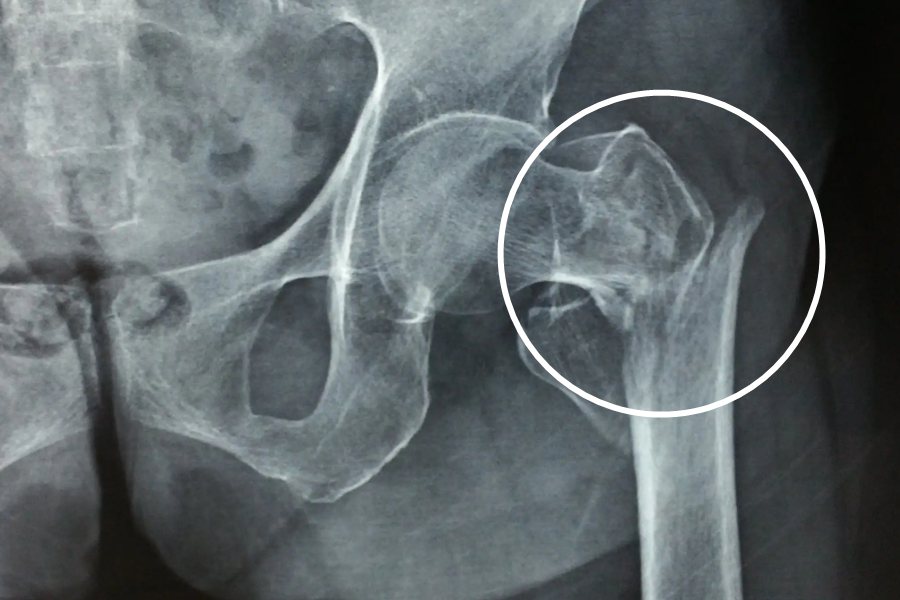

骨折主要是指骨完整性和连续性出现部分性或者是完全性的中断,骨折的基本特征包括畸形、异常活动以及骨擦感或是骨擦音。

骨折出现最直接的表现就是骨折处出现疼痛,当骨折部位位于四肢时,大多数会出现肢体畸形,活动受限,还可以触及骨折断端,若是开放性骨折还可以直接观察到骨折断端。骨折断端发生相互摩擦时可以感受到骨擦感和听见骨擦音。闭合性骨折位于出血较多的部位可以看见明显的肿胀和皮下瘀斑。出血量较大时,患者还会因为失血过多而面色苍白、心率和脉搏加快。部分患者在外伤后没有典型的骨折表现,但是会出现持续性难以缓解的局部疼痛,应该警惕。